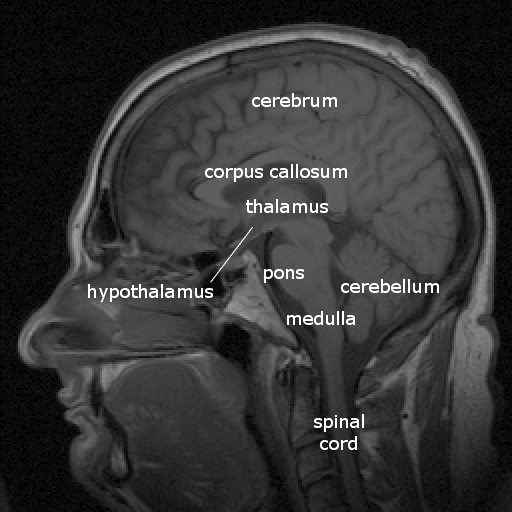

By Sebastian023, CC BY-SA 3.0, https://commons.wikimedia.org/w/index.php?curid=21020857

| Major division | Ventricular Landmark | Embryonic Division | Structure |

|---|---|---|---|

| Forebrain | Lateral | Telencephalon | Cerebral cortex |

| Basal ganglia | |||

| Hippocampus, amygdala |

| Third | Diencephalon | Thalamus | |

| Hypothalamus |

| Midbrain | Cerebral Aqueduct | Mesencephalon | Tectum, tegmentum |

| Hindbrain | 4th | Metencephalon | Cerebellum, pons |

| – | Mylencephalon | Medulla oblongata |